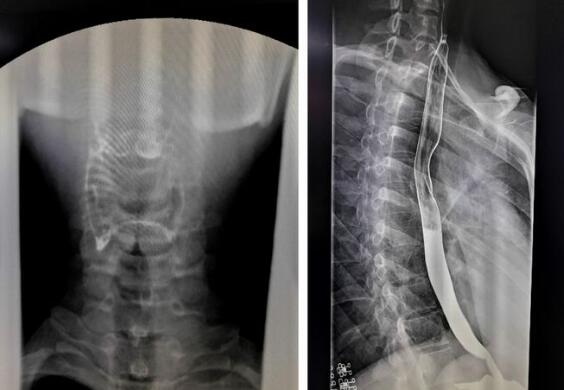

數字化胃腸機拍攝的上消化道造影圖

隨著數字化胃腸機臨床應用越來越廣泛,其功能性也大大增強,那么數字化胃腸機到底能做哪些檢查呢?其功能你有了解多少?1、上消化道造影,能顯示咽部到十二指腸的影像。